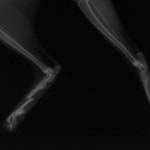

症例3:キルシュナーワイヤーのピンニングによる整復

ペルシャ猫 11ヶ月齢 雄

他院にて左大腿骨遠位の成長板骨折(salter-harrisⅠ型)が認められており、治療相談を目的として来院。当院にて、キルシュナーワイヤーを用いたピンニングにより骨折部位の整復を行いました。術後の経過は良好で、現在も経過観察中です。

術前レントゲン

術後レントゲン